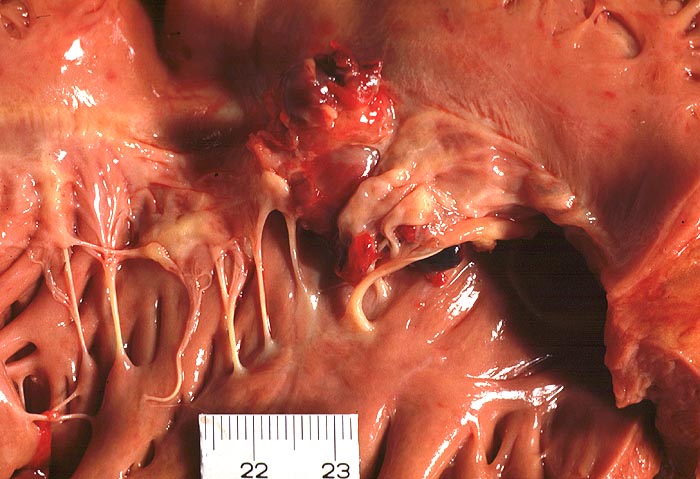

Makroskopisch sind entweder flache rötliche fibrinbelegte Ulzera (=ulcerosa (> 2935)) oder zusätzlich weiche gelbbraune bröcklige erbs- bis pflaumengrosse Polypen (=ulceropolyposa (> 2936) (> 8376)) oder ausschliesslich polypoide Fibrinbeläge (=marantica) auf einem Endokarddefekt oder einer partiell zerstörten Klappe erkennbar.

Mögliche Komplikationen einer infektiösen Endokarditis sind Klappenperforation (> 2934) oder Sehnenfadenruptur mit akuter Klappeninsuffizienz, Klappenstenose durch grosse Vegetationen, Übergreifen der Entzündung auf das Myokard, Dehiszenz von Klappenprothesen, Klappenvitium, Sepsis, septische (> 2120) oder sterile, häufig zerebrale Embolien, mykotisches Aneurysma und Glomerulonephritis.

• Längsschnitt durch Aorta, Aortenklappe und linkes Ventrikelmyokard.

• Oben im Bild die Aorta mit kleinem Fibroatherom.

• Abszedierende Entzündung der aortalen Adventitia ausgehend von septikopyämischen Streuherden.

• Ulzerierte Aortenklappe(ulcerosa).

• Dem ulzerierten Klappengerüst aufgelagerte polypöse Vegetation aus Fibrin und Granulozyten durchsetzt von blauen Kokkenbakterienkolonien (polyposa).